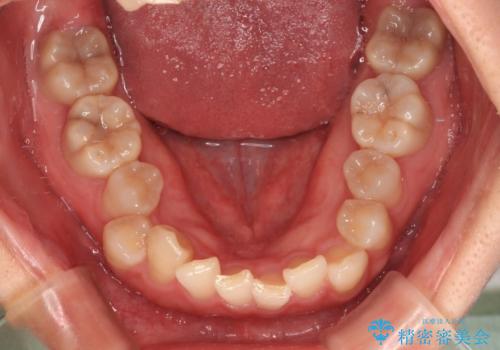

捻転の強い前歯 ワイヤー装置での非抜歯矯正

- 前歯のデコボコ、特に90度捻れている上顎前歯を気にして来院された患者様です。

マウスピースでもワイヤーでも対応可能でしたら、捻転が非常に強いことから、患者様と相談の上ワイヤー装置にて矯正治療を行うこととしました。

捻転を解消する際に、歯列全体が前方に突出して出っ歯の仕上がりとなることが懸念されたため、補助装置を用いて上顎歯列全体を後方に移動する力をかけることとしました。